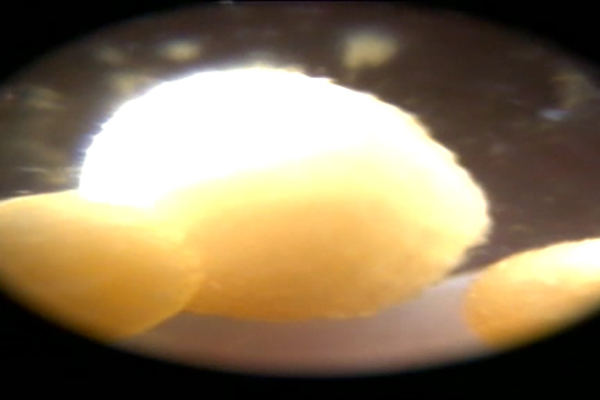

De behandeling viel voor onze dierenarts uiteindelijk wel wat tegen. Niet omdat het verwijderen van de blaasstenen via de scoop niet lukte, maar omdat er zo ontzettend veel blaassteentjes aanwezig bleken te zijn.